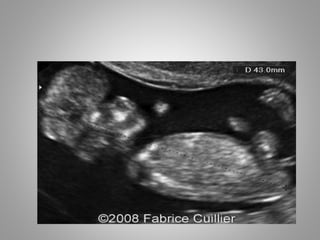

Usg Features

• Alobar and Semi-lobar types show absence of

falx and absent or non fused thalami.

• Alobar has 3 sub variants

1. Pan cake -Thin plate of cerebrum with large

dorsal Cyst

2. Cup - somewhat more tissue of cerebrum

with dorsal cyst

3. Ball – single mono-ventricle surrounded by

brain tissue of varied thickness.

Usg Features • Alobarand Semi-lobar types show absence of falx and absent or non fused thalami. • Alobar has 3 sub variants 1. Pan cake -Thin plate of cerebrum with large dorsal Cyst 2. Cup - somewhat more tissue of cerebrum with dorsal cyst 3. Ball – single mono-ventricle surrounded by brain tissue of varied thickness.